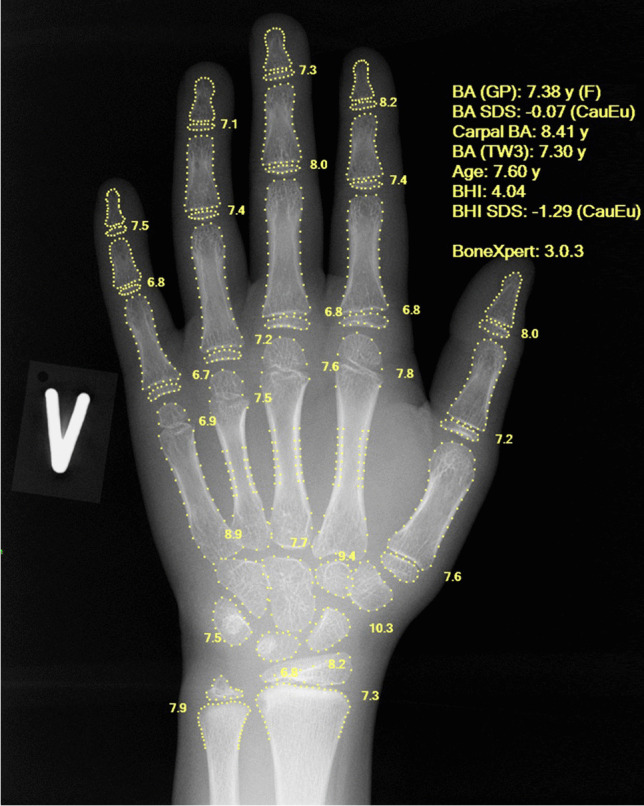

In this paper we investigated the adoption of AI in radiology, using the example of bone age assessment. Bone age is a measure of the maturity of the bones, and it is usually assessed from a hand and wrist radiograph (Fig. 1). The bone age, expressed in years, is the age at which half of the children in a reference population have attained the observed degree of maturation based on features such as the relative width of the epiphyses.

Fig. 1.

Dorsopalmar left hand radiograph in a 7.6-year-old girl following bone age assessment by BoneXpert. The output of the artificial intelligence (AI) system is an annotated Digital Imaging and Communications in Medicine (DICOM) file placed in the same study in the hospital’s picture archiving and communications system (PACS) as the original image. The algorithm has located the borders of the bones and assigned a Greulich and Pyle (GP) bone age to each of them. The average bone age (BA) for the 21 tubular bones is reported as “BA (GP): 7.38 y (F),” where the F indicates female gender, as taken from the DICOM header. The next line reports a bone age standard deviation score (SDS) of –0.07, which means that the bone age is 0.07 standard deviations below what is expected at that chronological age. Chronological age is indicated below the bone age SDS as 7.60 years (computed from the birth and study dates in the DICOM header). The remaining reported numbers are: carpal BA = the average bone age in the seven carpals, BA (TW3) = Tanner and Whitehouse version 3 bone age, BHI = bone health index, and its SDS relative to girls with the same bone age

The BoneXpert method (Visiana, Hørsholm, Denmark) for automated determination of bone age was launched in 2009 by the company Visiana [7]. The intended use is to completely replace the human rating of bone age, and in accordance with this, all clinical investigations during its development were performed with BoneXpert working as a standalone reader. The image analysis is based on traditional machine-learning methodology and involves prediction of bone age based on shape, intensity and texture scores derived from principal component analysis. The method attempts to locate almost all the bones in the hand and wrist (no sesamoid bones are included), as shown in Fig. 1, and determines an independent bone age value for each. A bone is rejected if its visual appearance falls outside the range covered in the machine learning process, or if its bone age value deviates by more than a predefined threshold from the average bone age determined from all the tubular bones. The threshold is set at 2.4 years for patients older than 7 years, then decreases linearly to 1.2 years at birth. The final bone age result is computed as an average of the accepted bones. The method rejects the image if there are fewer than eight accepted bones, to avoid the risk of the automated rating being wrong. This internal validation process is considered crucial for an AI-replace system. The software produces an annotated Digital Imaging and Communications in Medicine (DICOM) file (Fig. 1).